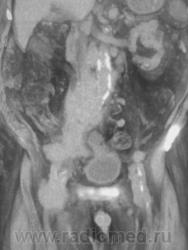

Мужчина 82 года, поступил в гнойное отделение с диагнозом: тромбофлебит? Правая нижняя конечность вдвое увеличена в объеме. Хирург отделения заподозрил опухоль таза с компрессией сосудов. По УЗИ - забрюшинная опухоль.         КТбрюшной полости: от L3 справа мягкотканная однородная опухоль с четкими ровными контурами, спускается в таз и на бедро. Плотность 45 ед.Н. Оттесняет мочевой пузырь, петли подвздошной кишки, не дифференцируется от нижней полой вены и подвздошных сосудов (нативно). Генерализованное поражение лимфоузлов брющной полости, паховые до 3-4 см. Гидронефроз справа, мочеточник оттеснен образованием значительно кпереди, на уровне L5 камень мочеточника 0.7см. Без контрастирования. Планировала на 5 апреля болюсное контрастирование, но пациента 2 апреля выписали!

Может, кто видел подобное? Велика вероятность злокачественной забрюшинной опухоли, но в 82 года такая генерализация лимфоузлов! Цитология паховых лимфоузлов в работе.

фронтальные реконструкции, плоскостные и объемные